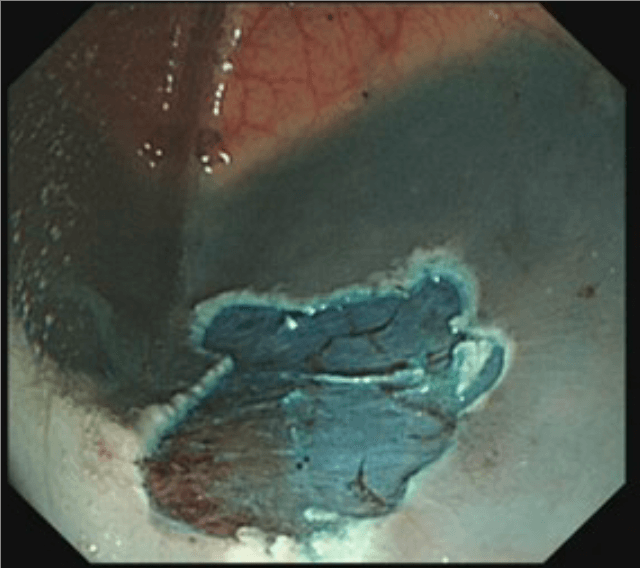

Colonoscopy involves passing a flexible tube (see image alongside) through the anus into the rectum and steering it around the colon. Some images of typical appearances are shown at the bottom of this page (hover over the images for a description).

The instrument channel can also be used for treatment purposes - for instance, to remove colonic polyps, or to cauterise bleeding blood vessels.